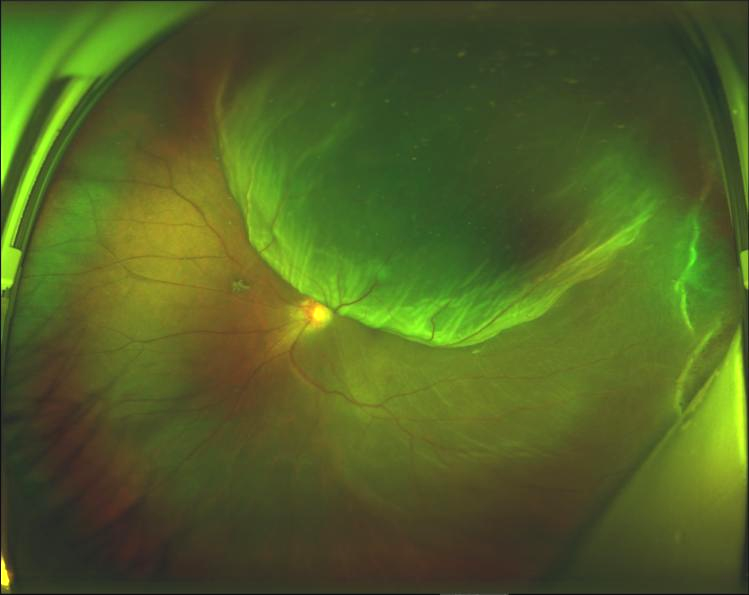

小曾術前眼底照相

折疊式人工玻璃體球囊鞏膜外頂壓術——為視網膜脫離患者帶來新選擇